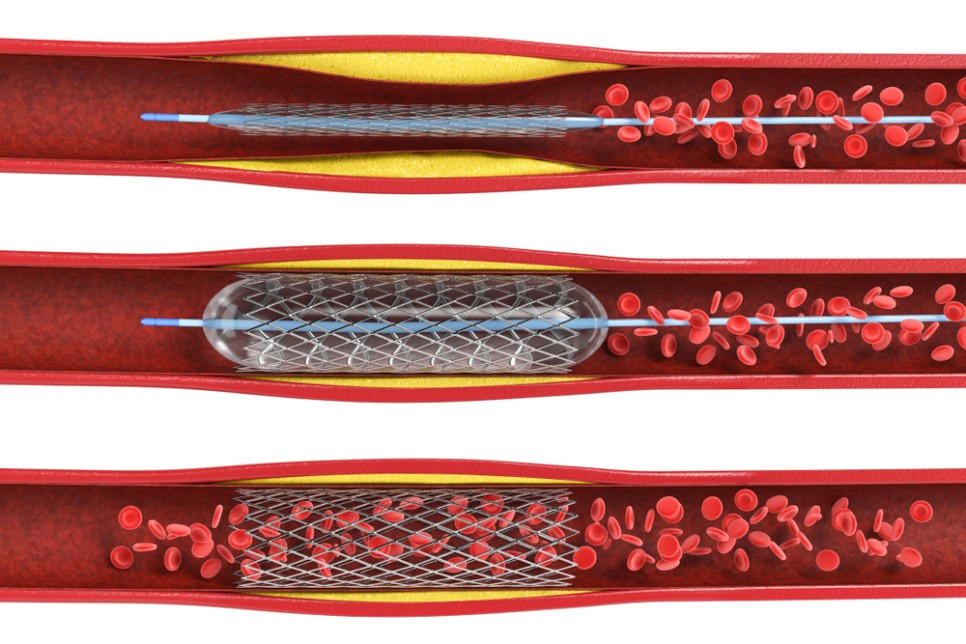

경동맥 협착증 시술은 스텐트를 이용하여 혈관을 확장하는 스텐트 확장술을 대표적으로 시행합니다. 전신마취가 어렵거나 심장병을 동반한 환자 등 수술이 위험한 경우에는 경동맥협착증 스텐트 시술을 시행합니다.

경동맥 스텐트 시술은 사타구니 동맥을 통해 가느다란 철선을 경동맥의 좁아진 부위를 통해 통과시킨 후 좁아진 부위를 풍선을 이용하여 조금 넓힌 후 스텐트 철망을 삽입합니다.